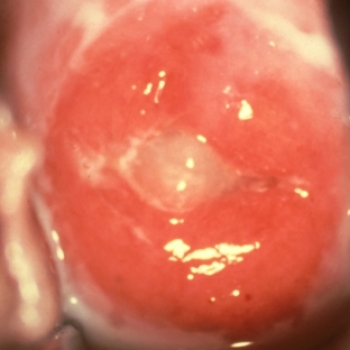

La primera manifestación consiste en un brote único, indoloro, que se ulcera con rapidez, ubicado en cualquier parte de los genitales masculinos; desaparece en unos días y usualmente pasa inadvertido.

La primera manifestación consiste en un brote único, indoloro, que se ulcera con rapidez, ubicado en cualquier parte de los genitales femeninos; desaparece en unos días y usualmente pasa inadvertido.

La primera manifestación consiste en un brote único, indoloro, que se ulcera con rapidez, ubicado en cualquier parte de la región anal; desaparece en unos días y usualmente pasa inadvertido.

Esta ubicación es poco frecuente y la primera manifestación consiste en un brote único, indoloro, que se ulcera con rapidez, ubicado en cualquier parte de la región oral; desaparece en unos días y usualmente pasa inadvertido.